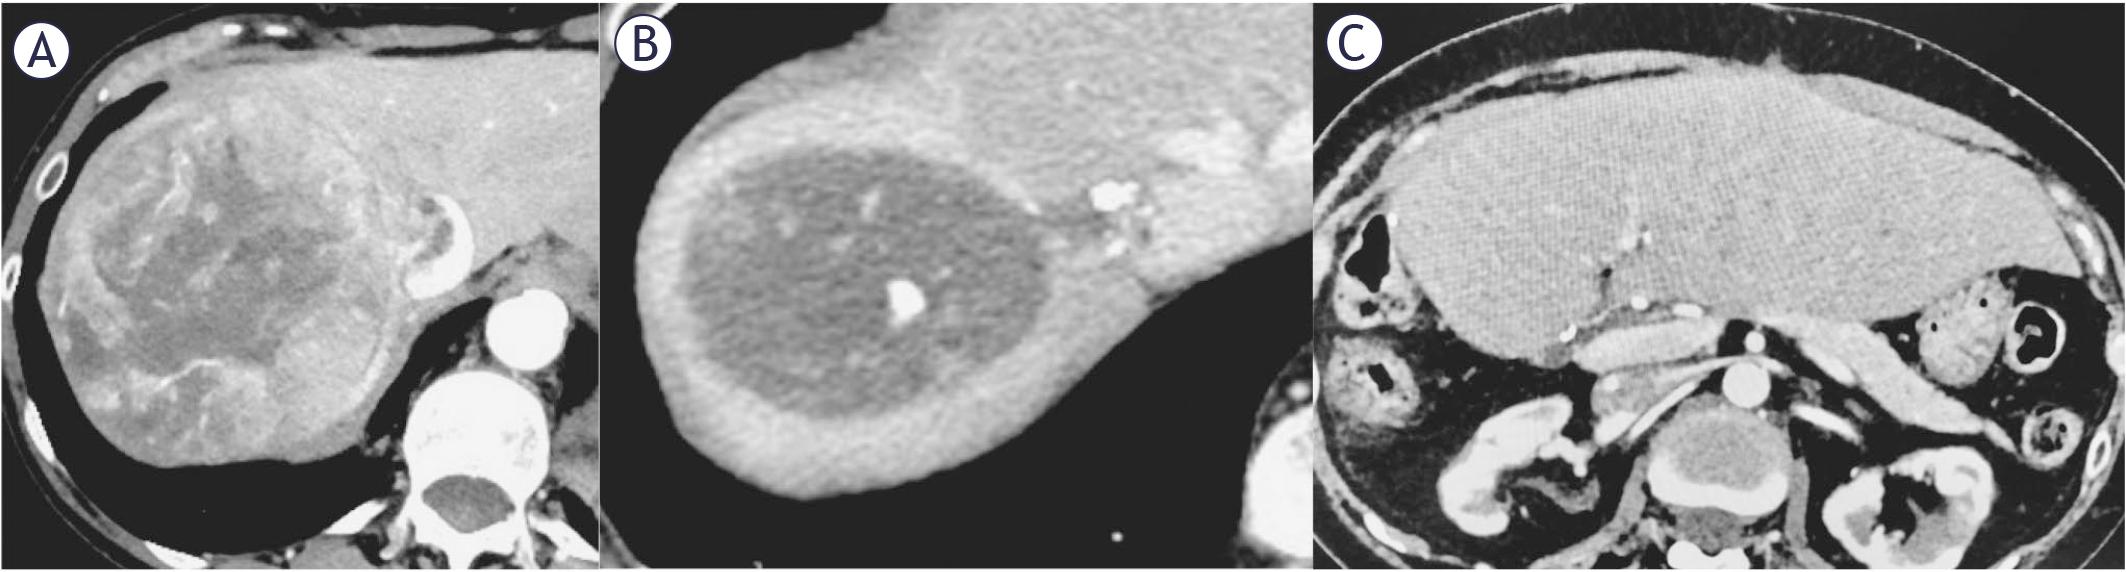

FIGURE 1.